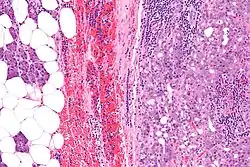

| Micrograph of an acinic cell carcinoma (right of image) and acinar glands (parotid gland - left of image). H&E stain. | |